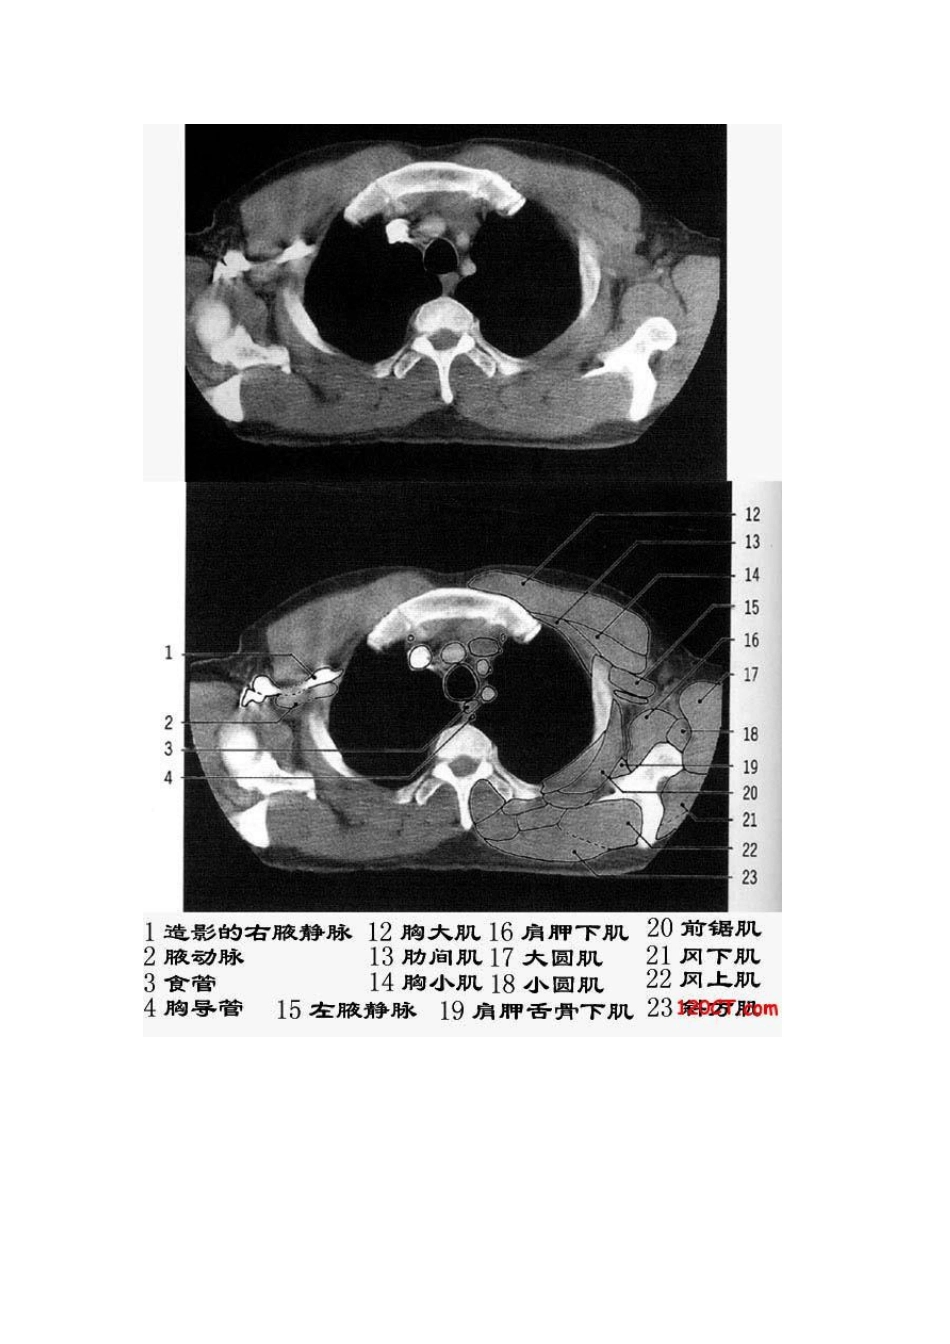

胸部CT解剖(软组织窗)